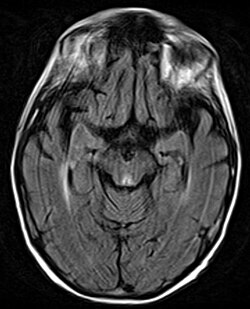

Амнезия (от греч. ἀμνησία — «забывчивость»), или утрата памяти, — это расстройство памяти, возникающее вследствие поражения головного мозга, заболеваний или психотравм. Временная амнезия может развиваться также после приёма седативных препаратов или снотворных средств. В зависимости от степени и локализации повреждения воспоминания могут утрачивать частично или полностью[1].

При антероградной амнезии нарушается перенос информации из кратковременной памяти в долговременную, что делает невозможным формирование новых воспоминаний. Эти два типа амнезии не являются взаимоисключающими и могут сочетаться у одного человека. Исследования показывают, что амнезия чаще всего связана с повреждением медиальных отделов височной доли. Амнезия также может быть индуцирована в состоянии гипноза при согласии гипнотизируемого лица. Важную роль в процессах памяти, прежде всего эпизодической, играет гиппокамп[2].

Черепно-мозговая травма включает любые повреждения или воздействия, приводящие к поражению головного мозга, и является наиболее частой причиной как ретроградной, так и антероградной амнезии. К таким повреждениям относятся травматическое повреждение мозга, возникающее, например, при падении или ударе по голове, инсульт и повреждение гиппокампа[4].